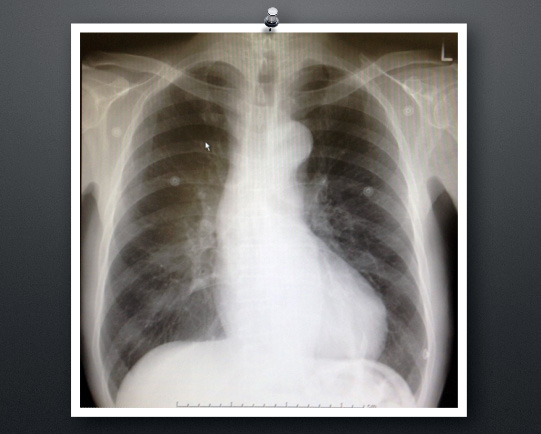

胸部レントゲンを提示します。

E146hcm_cpa_vf

クリックすると、拡大します。